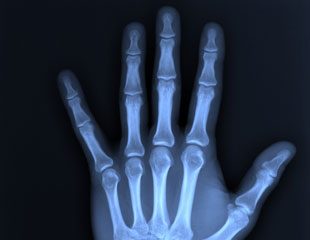

- Chụp X-quang xương khớp: Chẩn đoán gãy xương, trật khớp, thoái hóa khớp, viêm khớp, hoặc các dị tật bẩm sinh.

- Chấn thương xương khớp: X-quang là công cụ số một để xác định nhanh chóng và chính xác các vết gãy xương, rạn xương, trật khớp, hoặc các dị tật bẩm sinh.